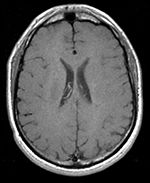

Unregistered baseline data: PD vs. T1Gd Unregistered followup data: PD exam 2 vs. exam 1

Registered baseline data Registered followup data